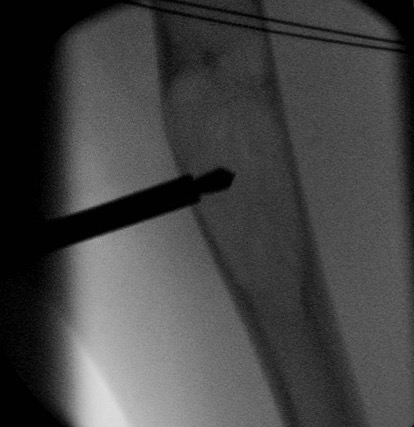

Bone marrow aspirate +/- demineralized bone matrix

Technique

GA / Aspirate from bone marrow

- inject into cyst under image intensifier